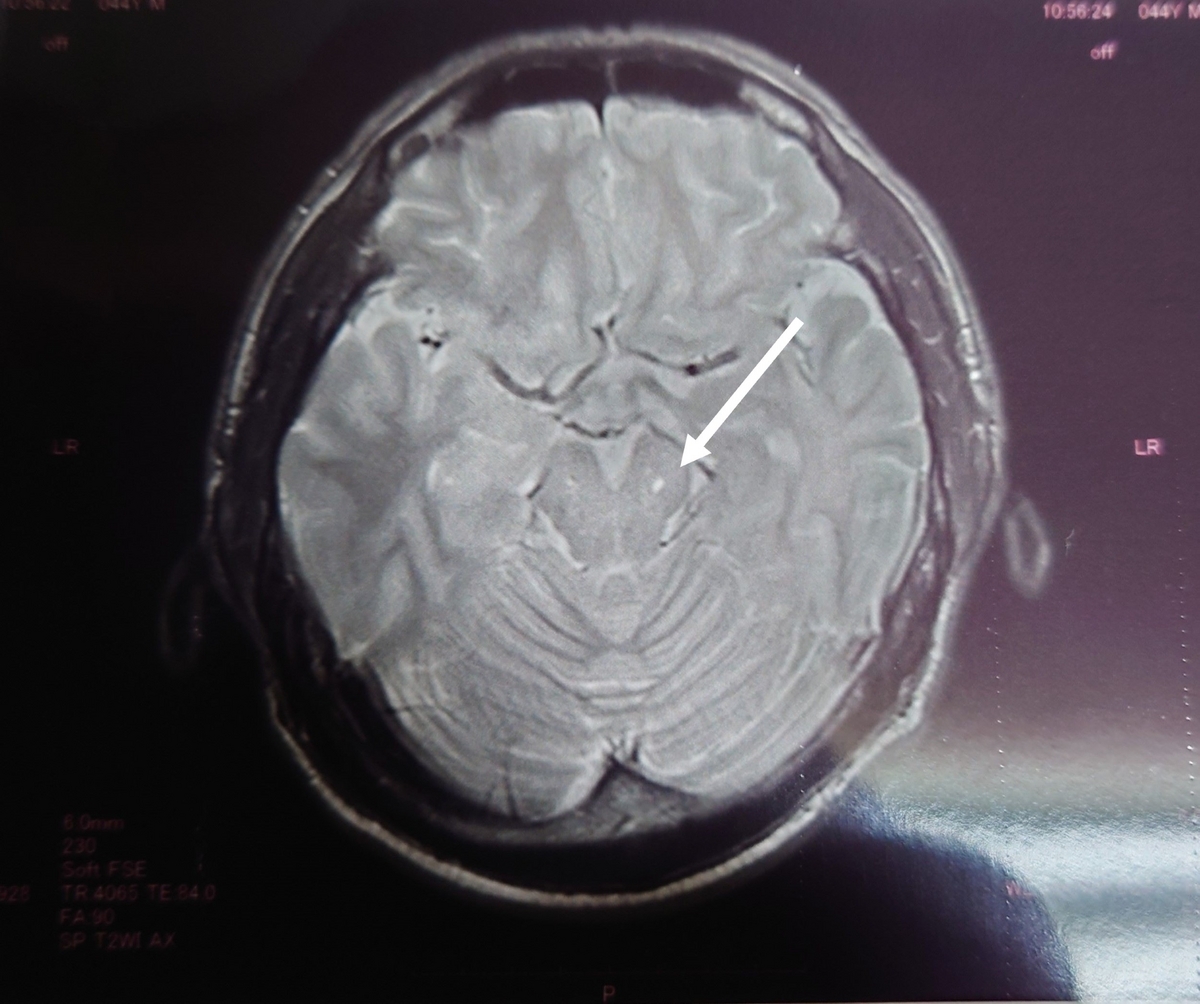

2020年の画像

2023年の画像(病院が違います)